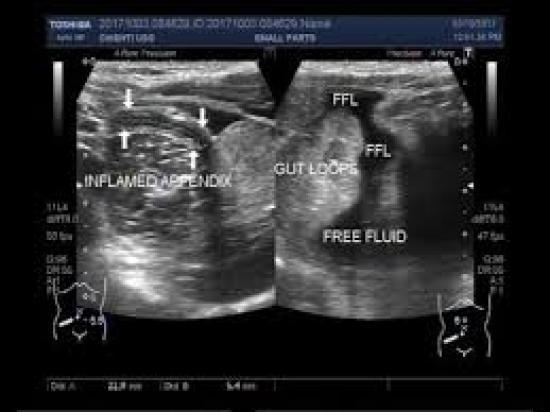

Imaging tests. Your doctor may also recommend an abdominal X-ray, an abdominal ultrasound or a computerized tomography (CT) scan to help confirm appendicitis or find other causes for your pain.